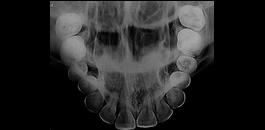

Indicada para avaliação detalhada das estruturas interproximais.

Indicada para visualização detalhada das estruturas dento-alveolares.